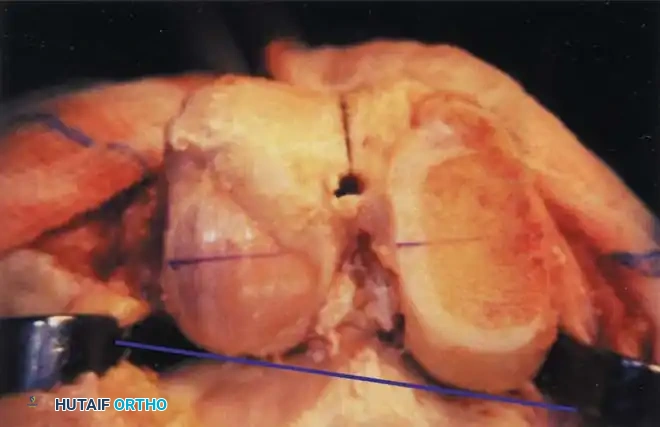

Femoral Rotational Alignment

The anterior and posterior femoral cuts determine the rotation of the femoral component and the shape of the flexion gap. This is arguably the most critical step in TKA.

Femoral component rotation can be determined using several anatomical and kinematic reference axes:

- The Surgical Transepicondylar Axis (TEA): Make the posterior femoral cut parallel to a line drawn between the prominence of the lateral epicondyle and the sulcus of the medial epicondyle.

- The Anteroposterior (AP) Axis (Whiteside's Line): Draw a line from the deepest part of the trochlear groove to the center of the intercondylar notch. The posterior femoral cut is made perpendicular to this axis.

- The Posterior Condylar Axis (PCA): When referencing the posterior condyles, the cut is typically made in 3 degrees of external rotation relative to a line connecting the most posterior aspects of the medial and lateral condyles.

⚠️ Pitfall: The Hypoplastic Lateral Condyle

In the valgus knee, the lateral femoral condyle is frequently hypoplastic. Relying solely on the posterior condylar axis in a valgus knee will lead to an internally rotated femoral component. In these cases, the TEA or AP axis must be prioritized.